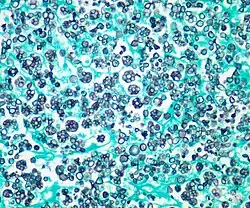

Parasitism

Prototheca and Helicosporidium are two unusual examples of once-algal organisms which have lost their chloroplasts and become parasitic. Prototheca infects vertebrates (including humans), and induces protothecosis; Helicosporidium infects a wide array of invertebrates.[9] Phyllosiphon is an unusual genus, consisting of branched siphonous filaments with chloroplasts. It is an endophytic parasite occurring in leaves, particularly the family Araceae.[17]

Photomicrograph (stained) of Prototheca wickerhamii infection in a human

Photomicrograph (stained) of Prototheca wickerhamii infection in a human -